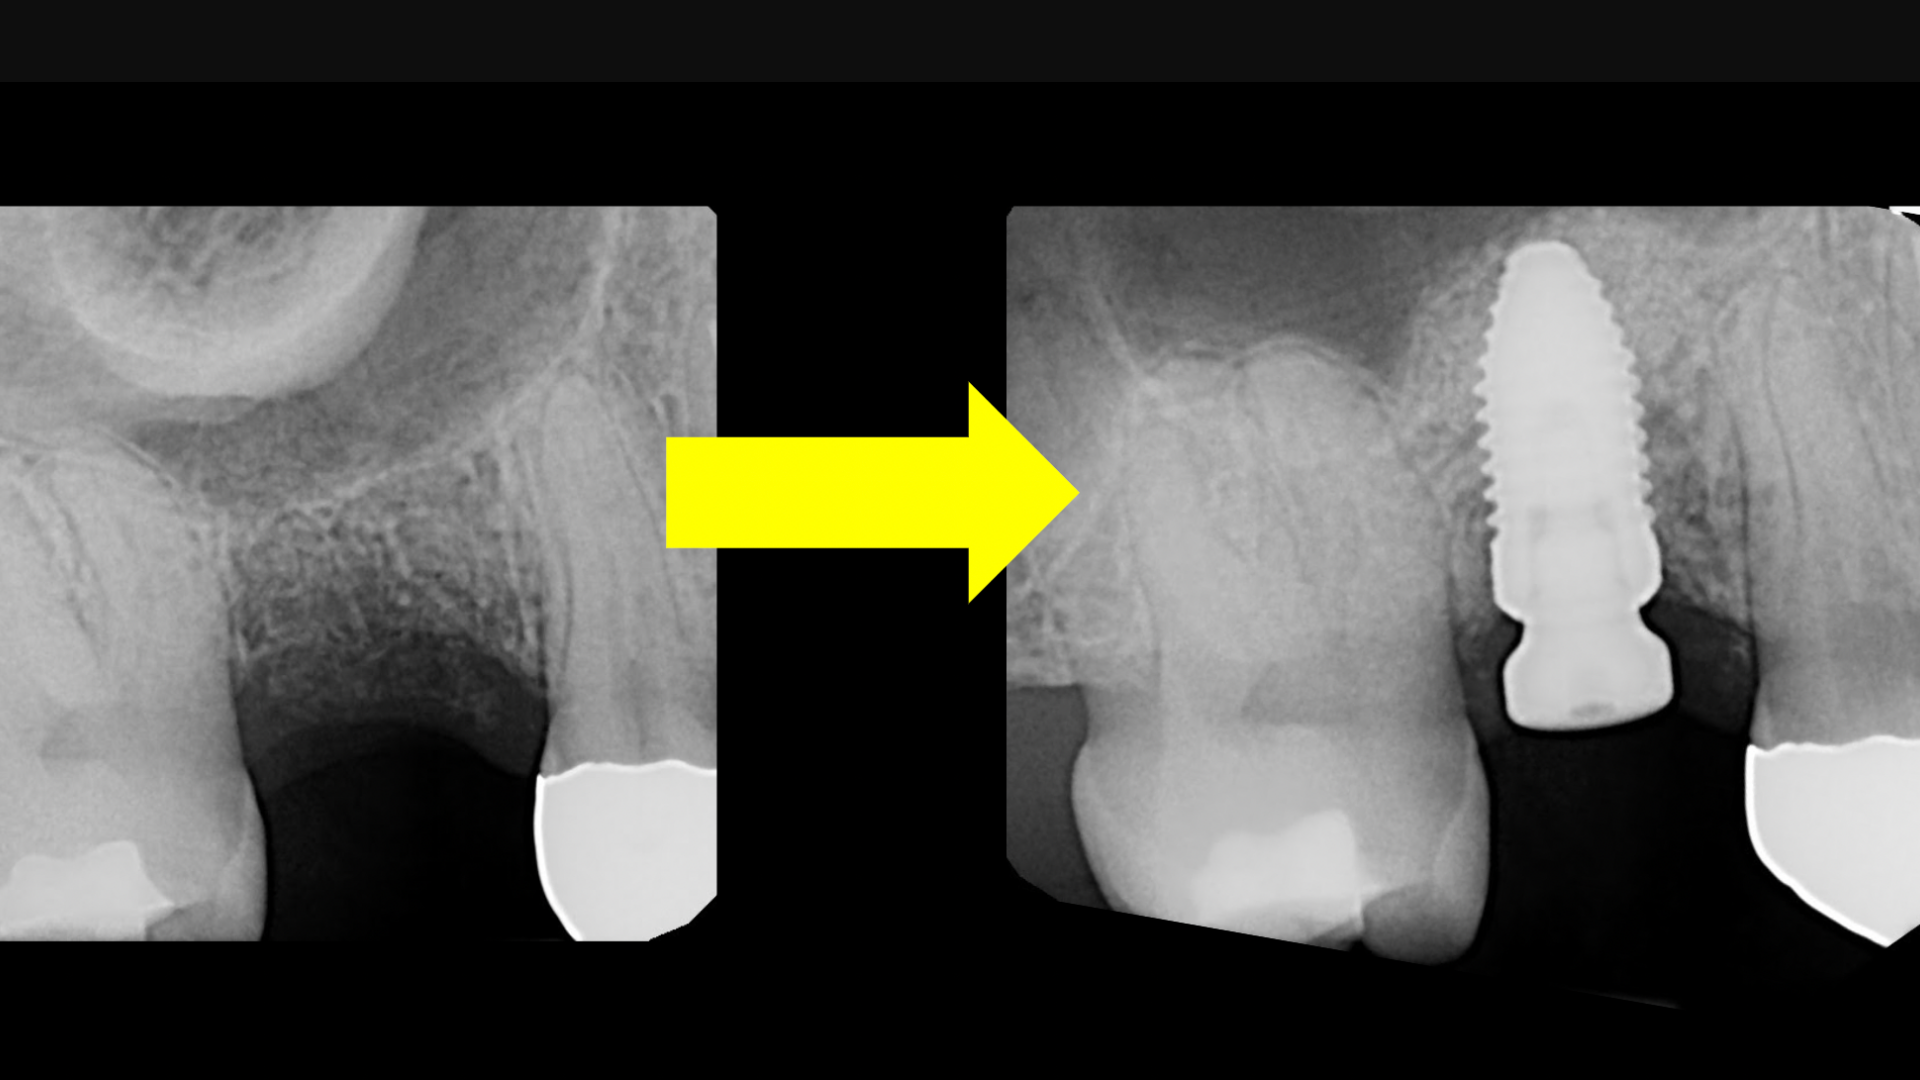

- How to diagnose the exact sinus lift method for each implant patient

- Step-by-step crestal sinus lifts.

- Step-by-step lateral window sinus lift